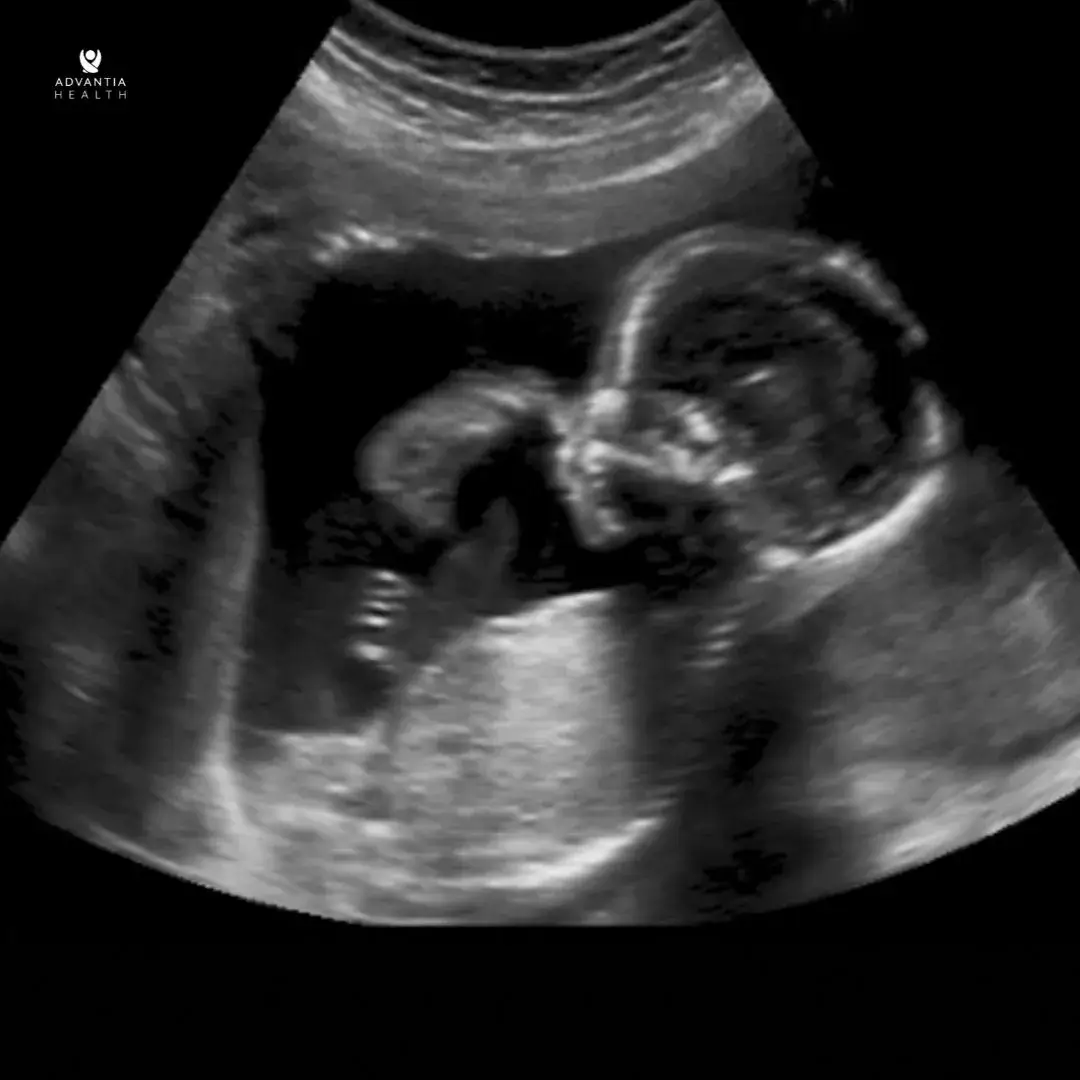

During the anatomy scan, a skilled sonographer will utilize ultrasound technology to capture detailed images of the fetus. This process involves examining various aspects, such as the baby’s head, brain, spine, heart, stomach, kidneys, bladder, and limbs. The scan will also check the fluid around the baby, placenta, and cervix position. This gives important information about how the pregnancy is going and the health of the mother and baby.

- Fetal Anatomy: A detailed assessment of the baby’s head, brain, spine, heart, stomach, kidneys, arms, legs, and more.